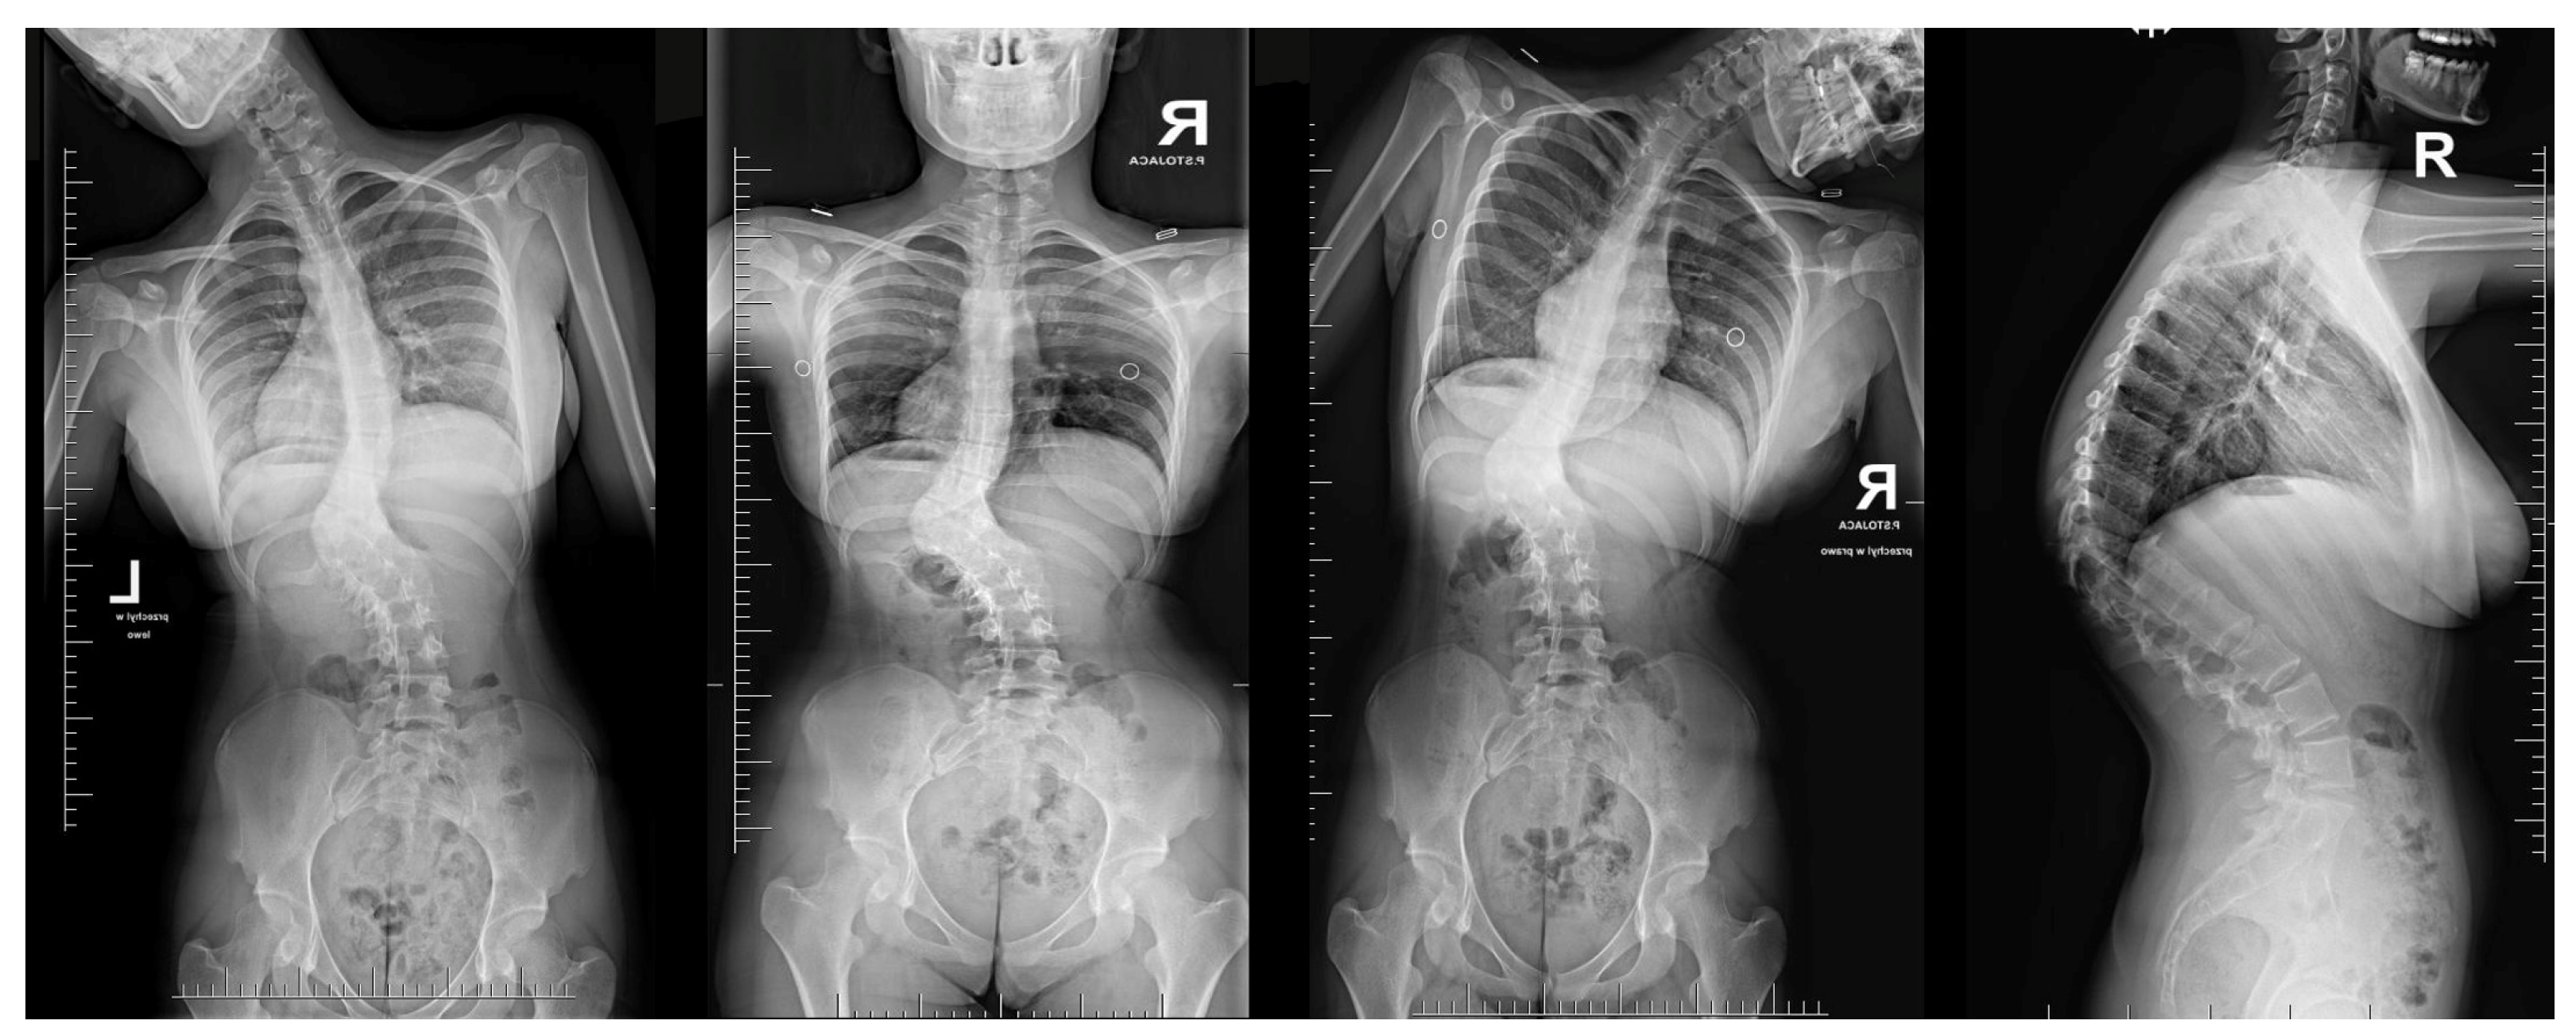

Neurological examinations showed full strength (5/5) in all major muscle groups of BUE/BLE, sensation intact throughout, normal reflexes (including abdominal), and pain on palpation in the thoracic spine above and below the gibbous. The neuro-imaging findings indicated a Cobb angle of 63° in the main thoracolumbar curve. The flexibility of the curve was measured at 63° when bending, decreasing to 48°. Additionally, there was a thoracic kyphosis of 4° between T2 and T5 and 32° between T5 and T12, with a severe focal thoracic kyphosis of 108° (Figure 2).

Figure 2. Standard standing AP and lateral X-rays and side-bending films of the 16-year-old female before surgical treatment. These X-rays showed severe and stiff congenital kyphosis.